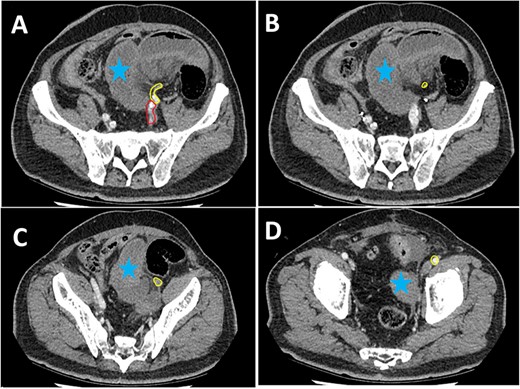

Three-dimensional reconstruction of the pre-operative (left) and post-operative (right) CT scan. The pre-operative CT demonstrates a segment of EIA that cannot be reconstructed due to the slow flow through the segment involved in the SBO (yellow arrow). The post-operative image demonstrates a patent EIA following vascular repair (blue arrow).

Pre-operative identification of internal hernias would allow for optimal management and planning, however diagnosis of intestinal herniation causing SBO on imaging can be challenging. CT features such as atypical bowel configuration, mesenteric abnormalities (including displacement, twisting or stretching of mesenteric vessels) and the position of surrounding viscera raise the index of suspicion of internal herniation [13]. In this case, retrospective review of the CT scan demonstrates the proximity and compression or partial occlusion of the segment of EIA within the closed-loop obstruction (Figs 3 and 4). This is concordant with our intra-operative findings of a narrow, non-pulsatile structure.